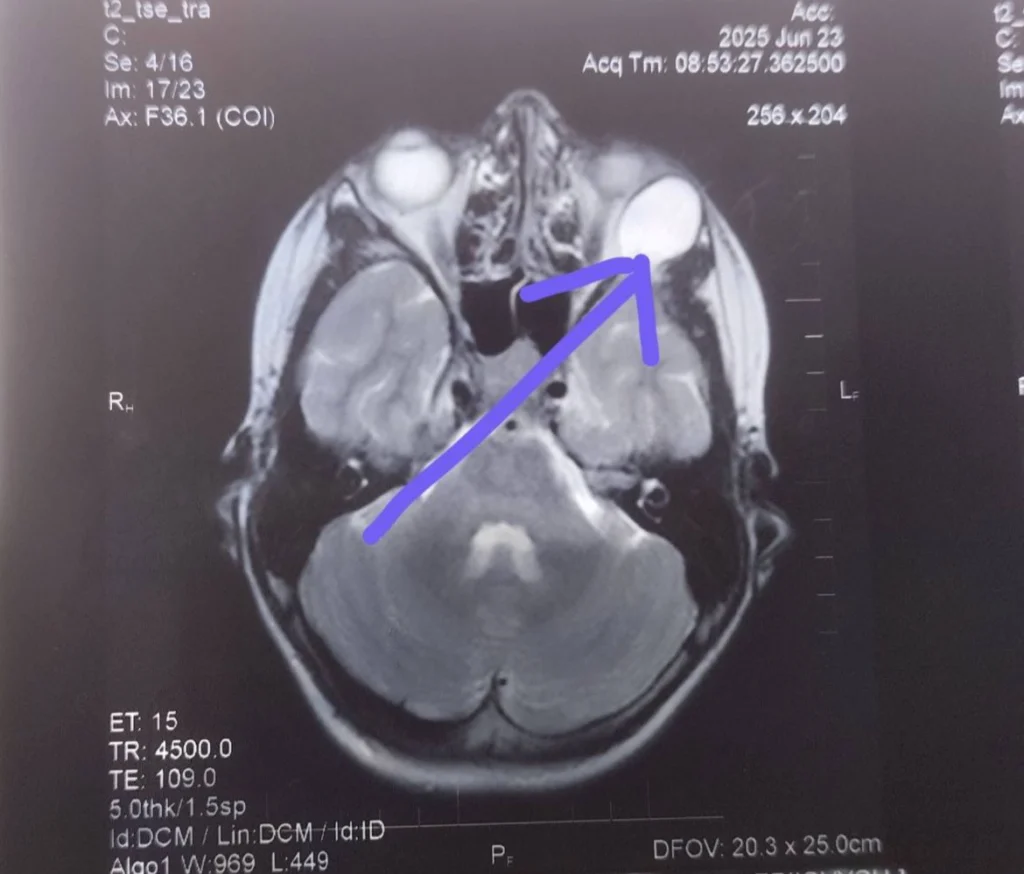

До Рівненської обласної дитячої лікарні звернувся 14-річний пацієнт із випинанням лівого ока, косоокістю та двоїнням предметів. Під час обстеження та МРТ було виявлено новоутвір очної ямки великих розмірів (приблизно 20 мм), який змістив очне яблуко та спричинив наявні симптоми.

Після операції стан пацієнта нормалізувався: положення ока відновилось, а двоїння зникло. Патогістологічне дослідження підтвердило діагноз – дермоїдна кіста.